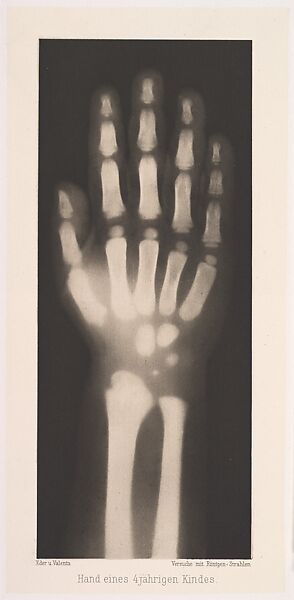

Versuche über Photographie mittelst der Röntgen'schen Strahlen

Eder was the director of an institute for graphic processes and the author of an early history of photography. With the photochemist Valenta, he produced a portfolio in January 1896, less than a month after Wilhelm Conrad Röntgen published his discovery of X-rays. Eder and Valenta’s volume, from which this plate derives, demonstrated the X-ray’s magical ability to reveal the hidden structure of living things. Human hands and feet, fish, frogs, a snake, a chameleon, a lizard, a rat, and a newborn rabbit are all presented in exquisitely printed photo-gravures, as are carved cameos and an assortment of natural materials. In an era when photography’s ability to accurately depict the visible world had become commonplace, this newfound capacity to record the invisible opened up a host of possibilities, both scientific and aesthetic. The careful compositions and shocking appearance of these “Experiments in Photography” link them to the previous century’s tradition of natural-history illustration and point toward the experiments of New Vision photographers in the 1910s and 1920s.

- Title: Versuche über Photographie mittelst der Röntgen'schen Strahlen

- Artist: Josef Maria Eder (Austrian, Krems an der Donau, 1855–1944 Kitzbühel) and

- Artist:  Eduard Valenta (Austrian, 1857–1937)

- Date: 1896

- Medium: Photogravures